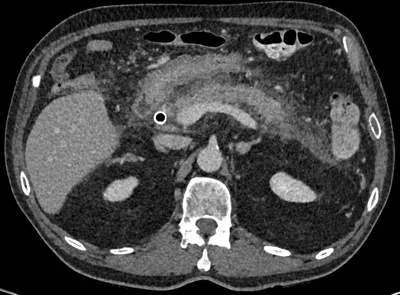

Pancreatitis post ERCP

CTAbdomenAxial+3

2/5/2026